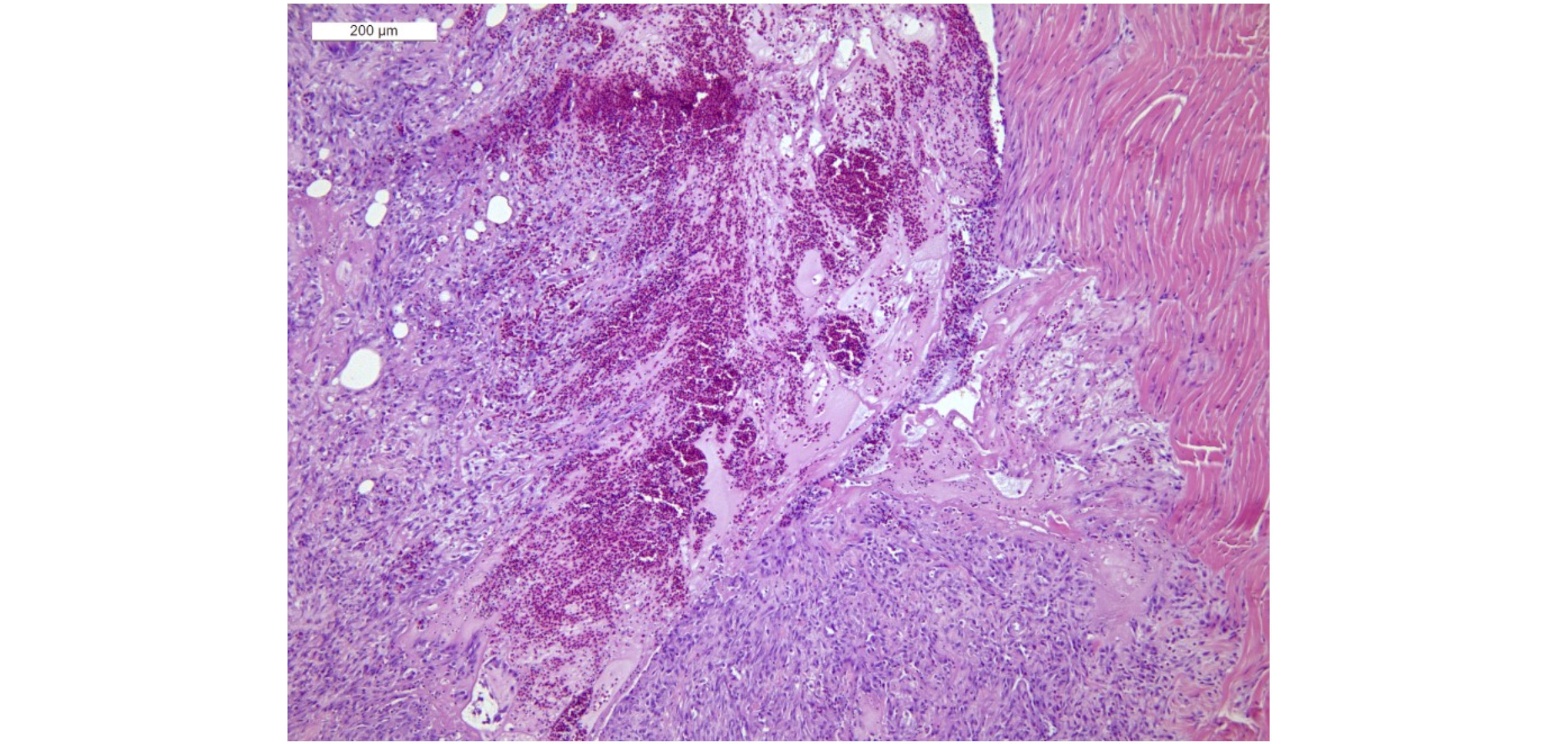

Histopathology

The drumsticks of Case 1 and Case 2 showed severe and diffuse tendon thickening due to fibrosis and lymphoplasmacytic and histiocytic infiltrate. A large fibrino-hemorrhagic area was also detected (Figure 8).

Figure. 8. Diffuse fibrosis around and within the tendon with lymphoplasmacytic and histiocytic infiltrate and fibrino-haemorrhagic area. Haematoxylin and Eosin (H E) staining. 10X.

The synoviocytes were hyperplastic with lymphoplasmacytic infiltrate and scant fibrinoheterophilic exudate in the synovial space (Figure 9).

Samples examined from Case 3 showed multifocal fibrosis and lymphohistiocytic infiltration of the tendon. For all the subjects a diagnosis of tenosynovitis of probable viral etiology was made. No bacterial elements were highlighted in the histological examined sections.